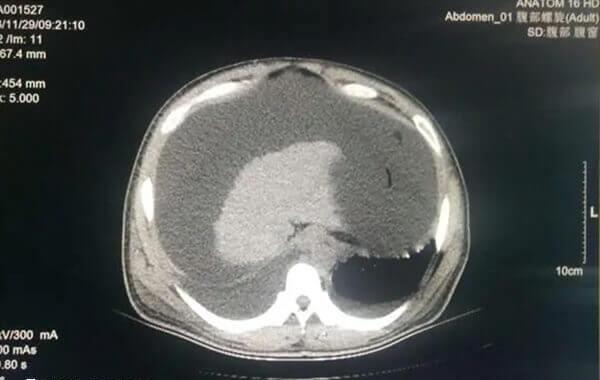

移植后的腹水对胎儿影响不是很大,但是对母亲具有一定的危害性。如果移植后出现腹水,多见于卵巢过度刺激综合征,就是体内超促排卵,是多个卵泡发育导致的试管婴儿的一种并发症,这类患者常常会表现为腹水、胸水、尿量减少等。虽然大部分腹水症状很轻微,但在某些情况下可能会引起下列并发症: